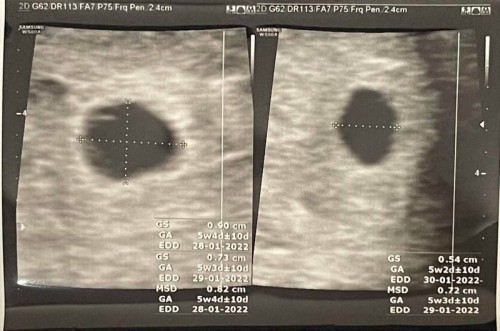

ท้องแรก ตั้งครรภ์ได้ 5 วีคกว่าๆ มีเลือดสีน้ำตาลอ่อนออกค่อนข้างเยอะ คุณหมอแจ้งว่าภาวะแท้งคุกคาม ฉีดยาผยุงครรภ์ และให้ยามากินต่อ และให้เดินให้น้อยที่สุดค่ะ ภาพอัลตราซาวด์คุณหมอบอกว่า มีจุดเลือดคลั่งใกล้ถุงตั้งครรภ์ค่ะ หลังจากฉีดยามา เลือดก็ไม่มีออกมาแล้ว แต่ปวดท้องน้อยจี้ดๆซ้ายที ขวาทีค่ะ ค่อนข้างกังวลมากเลยค่ะ คุณแม่ท่านไหนมีปประสบการณ์คล้ายๆกัน ตอนนี้เป็นยังไงบ้างค่ะ #ขอบคุณล่วงหน้านะคะ